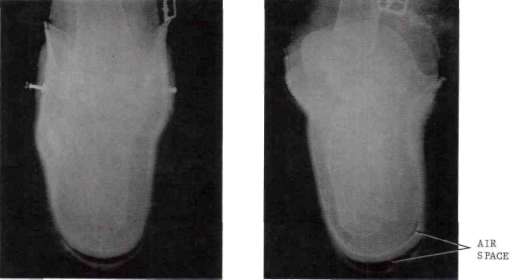

Although X-ray films obtained by routine methods, without the use of a contrast medium, provide considerable useful information about stump-socket fit, they do not always reveal a clear demarcation between the soft tissues and the socket. This observation was confirmed in the present study on comparing films made with and without a contrast medium taken on the same patient, using the same X-ray settings for both series. With few exceptions, the contrast-medium films were superior to the routine films in outlining the periphery of the stump more sharply. An example of this superiority may be seen in comparing the two views in Fig. 4. This improvement in the delineation of the stump-socket interface makes it easier to read the films and eliminates any doubts that may arise concerning the exact relationship between the stump and the socket at various stump levels.

Figure 4: